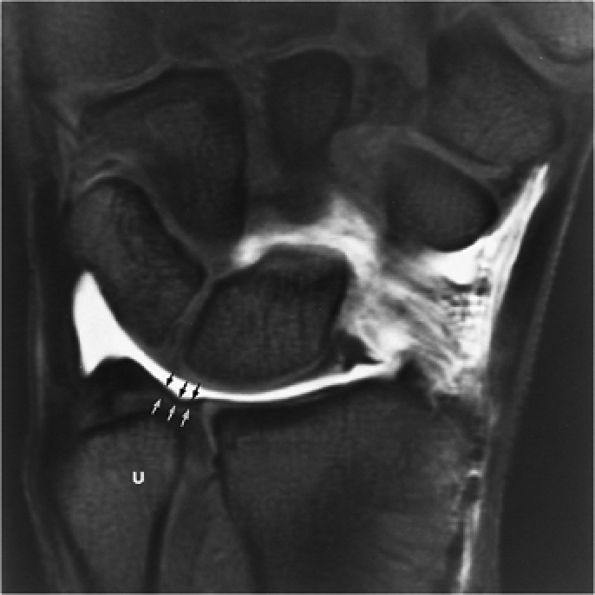

FIGURE 10.35 LUNOTRIQUETRAL LIGAMENT.

|